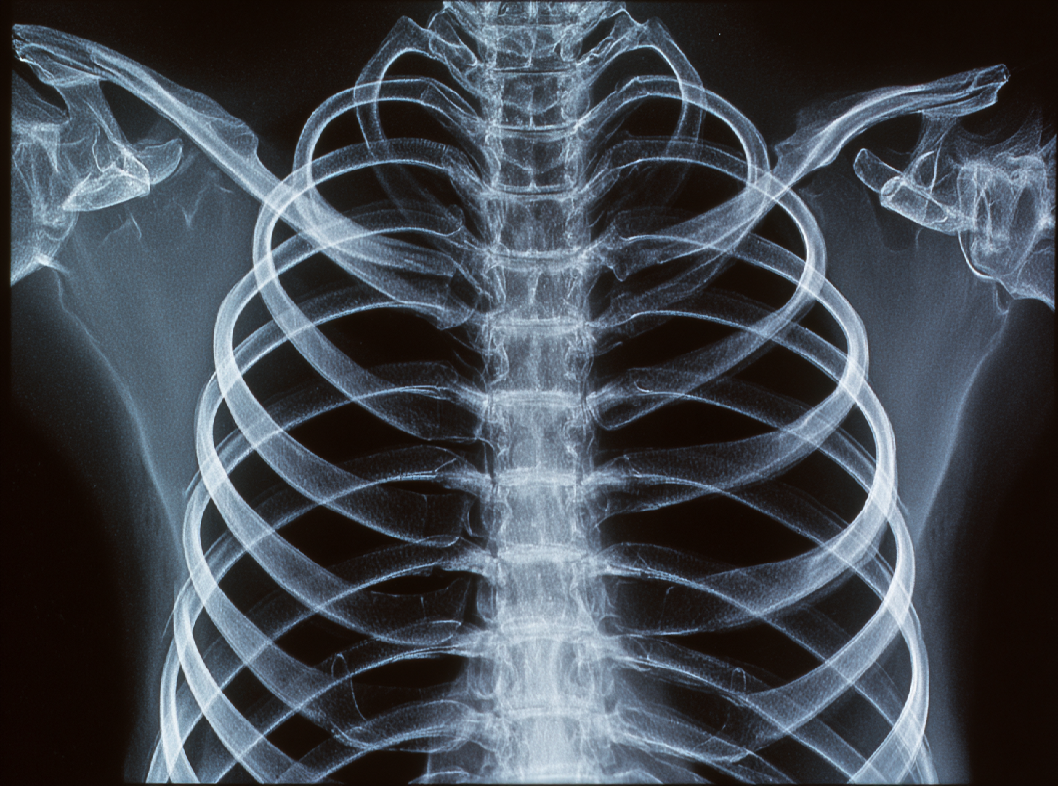

Клинические проявления ПР включают в себя боль в области повреждения, усиливающуюся при дыхании, кашле или движении тела. Часто можно наблюдать отек и синяк в месте перелома. Диагностика осуществляется при помощи клинического осмотра, рентгенографии и в некоторых случаях компьютерной томографии.

Перелом ребра (ПР) представляет собой повреждение структуры ребра, которое может возникнуть в результате травматического воздействия или сильного механического воздействия на грудную клетку. Рёбра являются костными элементами, образующими скелет грудной клетки, и их переломы могут иметь разнообразные характеристики в зависимости от механизма травмы.